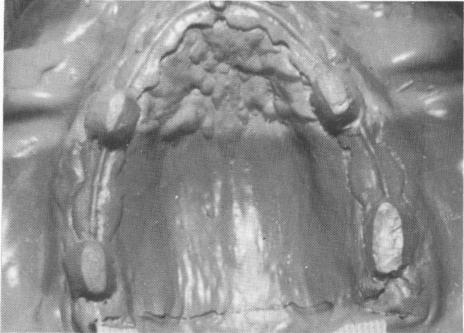

Fig. 10-268. A full arch rubber base impression was taken.

2 Maxillary full arch rubber base impression